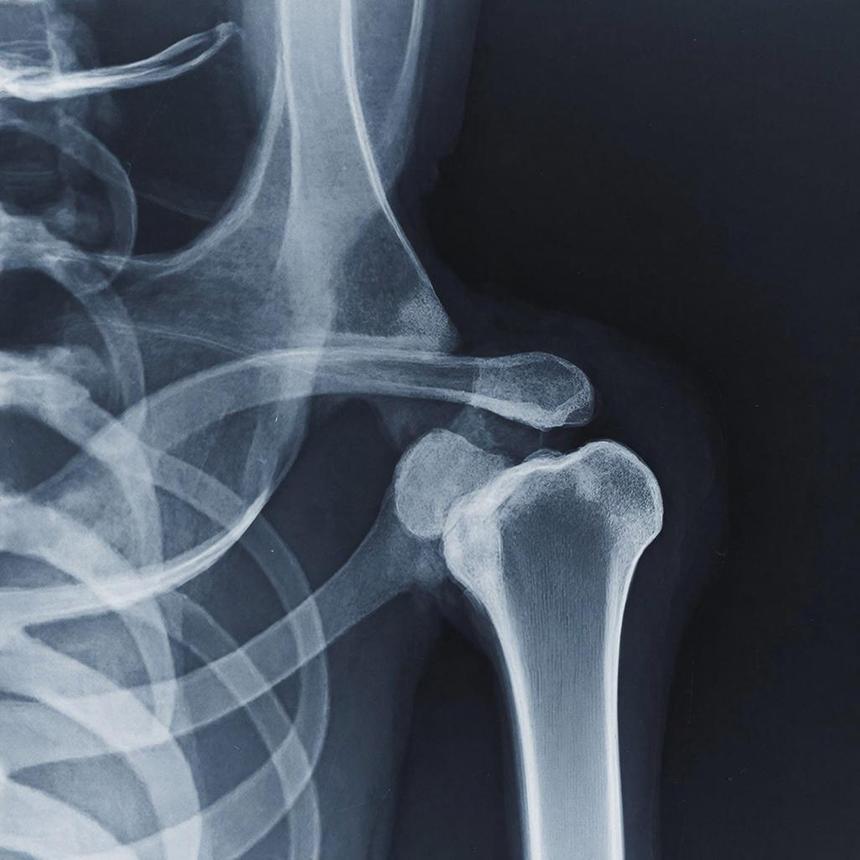

Сферические кластеры (сфероиды) смешивали с β-трикальцийфосфатом. Затем эту смесь транспортировали к позвонкам L4 и L5 у крыс с переломами позвоночника. Причиной же переломов стал остеопороз.

У группы крыс, которую лечили остеогенными сфероидами, значительно увеличилась костная масса, улучшились показатели сращения и механическая прочность. Согласно гистологическому анализу, происходило усиленное образование новой костной ткани, интеграция β-трикальцийфосфата.